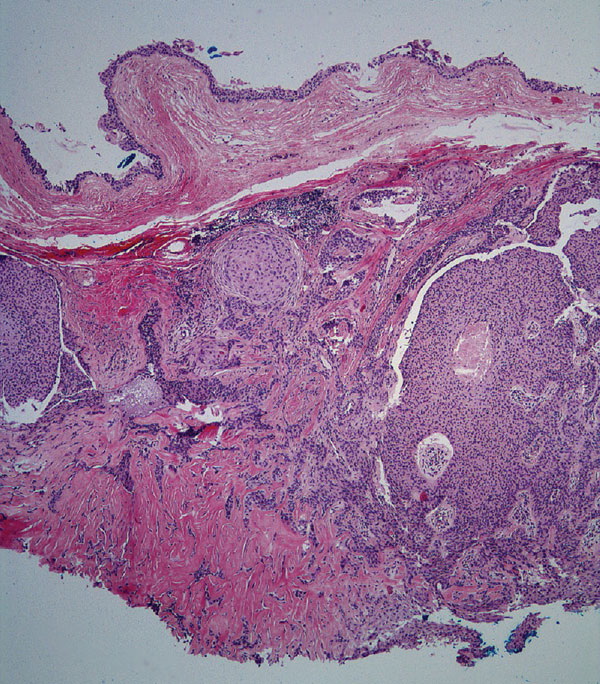

Hidradenoma_Malignant = الغدوم العرقي الخبيث